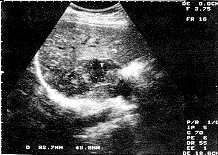

中国超声医学杂志990139 患者,女性,30岁,一个月余明显向心性肥胖(满月脸、水牛背)、皮肤紫纹、多毛等。来我科B超检查。超声表现:右肾上腺区域见9.3cm×4.9cm包块、边界多呈清楚的高回声,表面欠平整,呈分叶状,内部呈强弱不均质回声(附图)。B超诊断:右肾上腺皮质腺癌。患者在上级医院手术及病理诊断同超声。

附图 右肾上肾皮质腺瘤 T:肿瘤

讨论:肾上腺皮质腺癌声像图在肾上腺区显示大于3cm的分叶状实质性肿块,结合临床有明显的皮质醇增多症或肾上腺性征异常,应首先考虑肾上腺皮质恶性肿瘤的可能。肿瘤体积越大,诊断的准确性越高。所以,对瘤体大小、超声所见和临床表现三者的综合分析是诊断肾上腺皮质腺癌的主要关键,以提高对本病诊断的正确率。